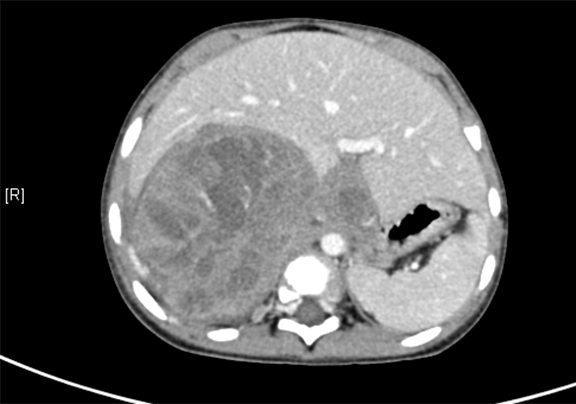

上腹部增强CT示:肝右后叶-右肾上腺区-右肾上极区域占位,考虑恶性肿瘤,肝母细胞瘤?并腹膜后转移。

将0.625mm双源薄层CT资料的静脉期和动脉期Dicom格式文件导入海信CAS系统。

通过调节窗宽窗位调整CT序号,对肿瘤,肝实质,胆囊,下腔静脉,肿瘤,肝动脉、门静脉及肝静脉等进行三维重建;系统自动计算肿瘤体积和肝脏体积。

模拟手术操作,自动计算切除肿瘤体积。肝脏体积为660.9ml,肿瘤体积为812.3ml,肿瘤体积为肝脏体积的122.9%,通过比对3-4岁正常肝脏体积为522.63±121.24 ml,肿瘤所占比例较大,且包裹右侧肾脏、及腹腔大血管,手术无法完整切除肿物,不建议给予手术治疗。

术前CT检查:

动脉期

静脉期

平衡期